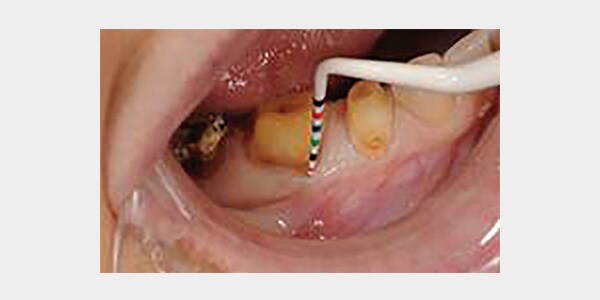

Hu-Friedy's Colorvue® Line of Probes feature a distinct color-coding design, offering a reliable and efficient solution to evaluate a patient's periodontal status. Offering high contrast and varied color millimeter markings, it takes the strain out of the clinician's eyes offering better visibility in intra-oral structures. Colorvue® line's rounded resin tips provide the optimal level of flexibility which ensures a more comfortable patient experience. Colorvue® tips are ideal for the delicate implant attachments as well. As an extra plus, the tips provide greater value to the office as they can be replaced, and each tip can be sterilized and used up to 30 times!

• Colorvue probes provide a fast and accurate evaluation of pocket depth and recession

• Tips are marked with vivid yellow and black color codes, enhancing contrast to intraoral structures

5 mm of recession is easily assessed as a result of the excellent contrast between the Colorvue probe and exposed root surface. In addition, the Colorvue probe enhances measurement of periodontal attachment loss.